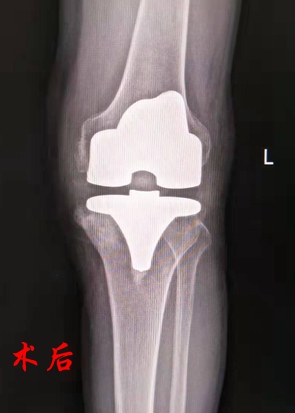

术前,关节科团队为黄大伯详细做了检查。因黄大伯同时伴有心脏病、胃病、酒精肝,为保证手术顺利进行,关节科邀请综合内科、手术室、麻醉科等科室联合会诊,进行术前综合评估,并制订了详细的手术和术后恢复方案。3天后,刘卓华院长带领关节科专业团队为黄大伯实施了左侧人工膝关节置换术。该患者由于病程长、关节磨损严重,内侧平台骨缺损严重,因此手术最大的难点是要求操作精细,历经1个半小时,手术顺利完成。术后黄老伯生命体征平稳,第二天在专业康复师的指导下借助助行器行走。

人工膝关节置换术是用人工假体取代已严重损坏而不能行使正常功能的膝关节表面,该手术适用于膝关节骨性关节炎、类风湿性关节炎、创伤性关节炎、骨缺血坏死或肿瘤等病变所致的严重疼痛和(或)功能障碍,能非常有效地缓解晚期膝关节病痛,改善膝关节功能,纠正膝关节畸形,极大地改善病人的生活质量,它是目前膝关节疾病最佳的治疗方法。